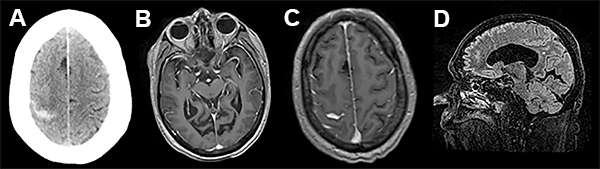

Se decidió internación para valoración clínica y por imágenes. Por resonancia se evidenció colección de LCR en el sitio de la reparación dural (fig. 1).

Figura 1

A las 72 hs de la segunda intervención comienza con cefaleas intensas, náuseas, trastorno del sensorio por lo cual se realiza nueva internación, evidenciando mediante TAC sangrado subaracnoideo (fig. 2).

Figura 2

En el presente trabajo, los autores reportan un evento hemorrágico cerebral como complicación de una fistula de líquido cefalorraquídeo (LCR) asociada a una cirugía espinal lumbar mini invasiva. Dicho evento se desencadenó 72 hs luego de la reparación de la fístula de LCR, presentándose como una hemorragia subaracnoidea de la convexidad cerebral. Esta complicación ha sido descrita por numerosos grupos,1-5 siendo la localización mas frecuente el cerebelo. Si bien las imágenes de tomografía y resonancia magnética nuclear evidencian la presencia de hemorragia subaracnoidea en el surco central derecho, llama la atención la asimetría de surcos con hipodensidad en el área premotora derecha, similar a los hallazgos asociados con una trombosis venosa. Más aún, considerando que el paciente tiene antecedentes de trombosis venosa profunda e ingresa a las 72 horas por trastornos del sensorio (difícilmente explicables sólo por una hemorragia subaracnoidea de la convexidad), no podemos descartar con las imágenes brindadas la presencia de trombosis venosa, complicación también descripta como consecuencia de una perdida de LCR.6-9 Si bien ambas complicaciones son de muy baja ocurrencia, es importante reconocer su existencia a la hora de evaluar un postoperatorio de cirugía espinal complicado con fistula de LCR en pacientes añosos.